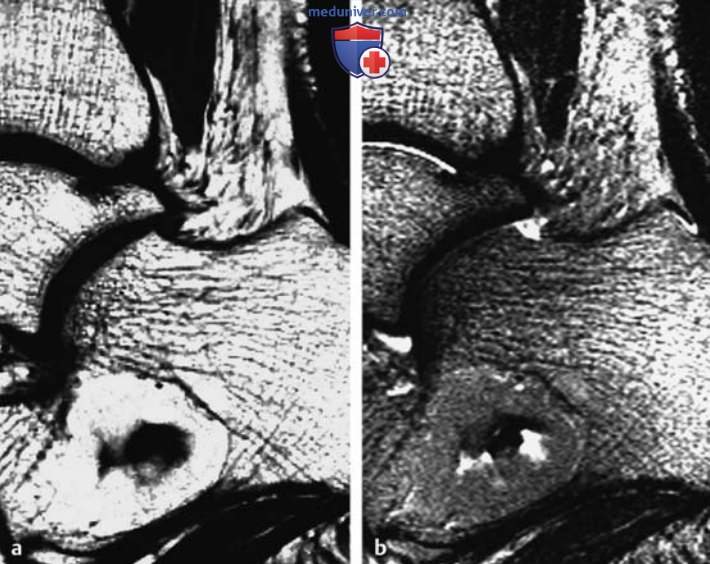

МРТ доброкачественных опухолей костей и опухолеподобных поражений

Рисунок 4. а, b Остеохондрома подвздошной кости, расположенная на ножке.

а Т1в-SE-изображение во фронтальной плоскости.

b Т2в-БЕ-изображение в аксиальной плоскости.

Отмечается непрерывный переход костномозговых пространств и кортикального слоя подвздошной кости на ножку патологического образования. Хрящевая шапочка имеет максимальную толщину примерно 1 см. Она изоинтенсивна мышцам на Т1 в-изображениях и сильно гиперинтенсивна на Т2в-изображениях. На Т2в-изображениях гиалиновый хрящ отделен от окружающих мягких тканей слабо гипоинтенсивным окаймлением (головки стрелок, b).